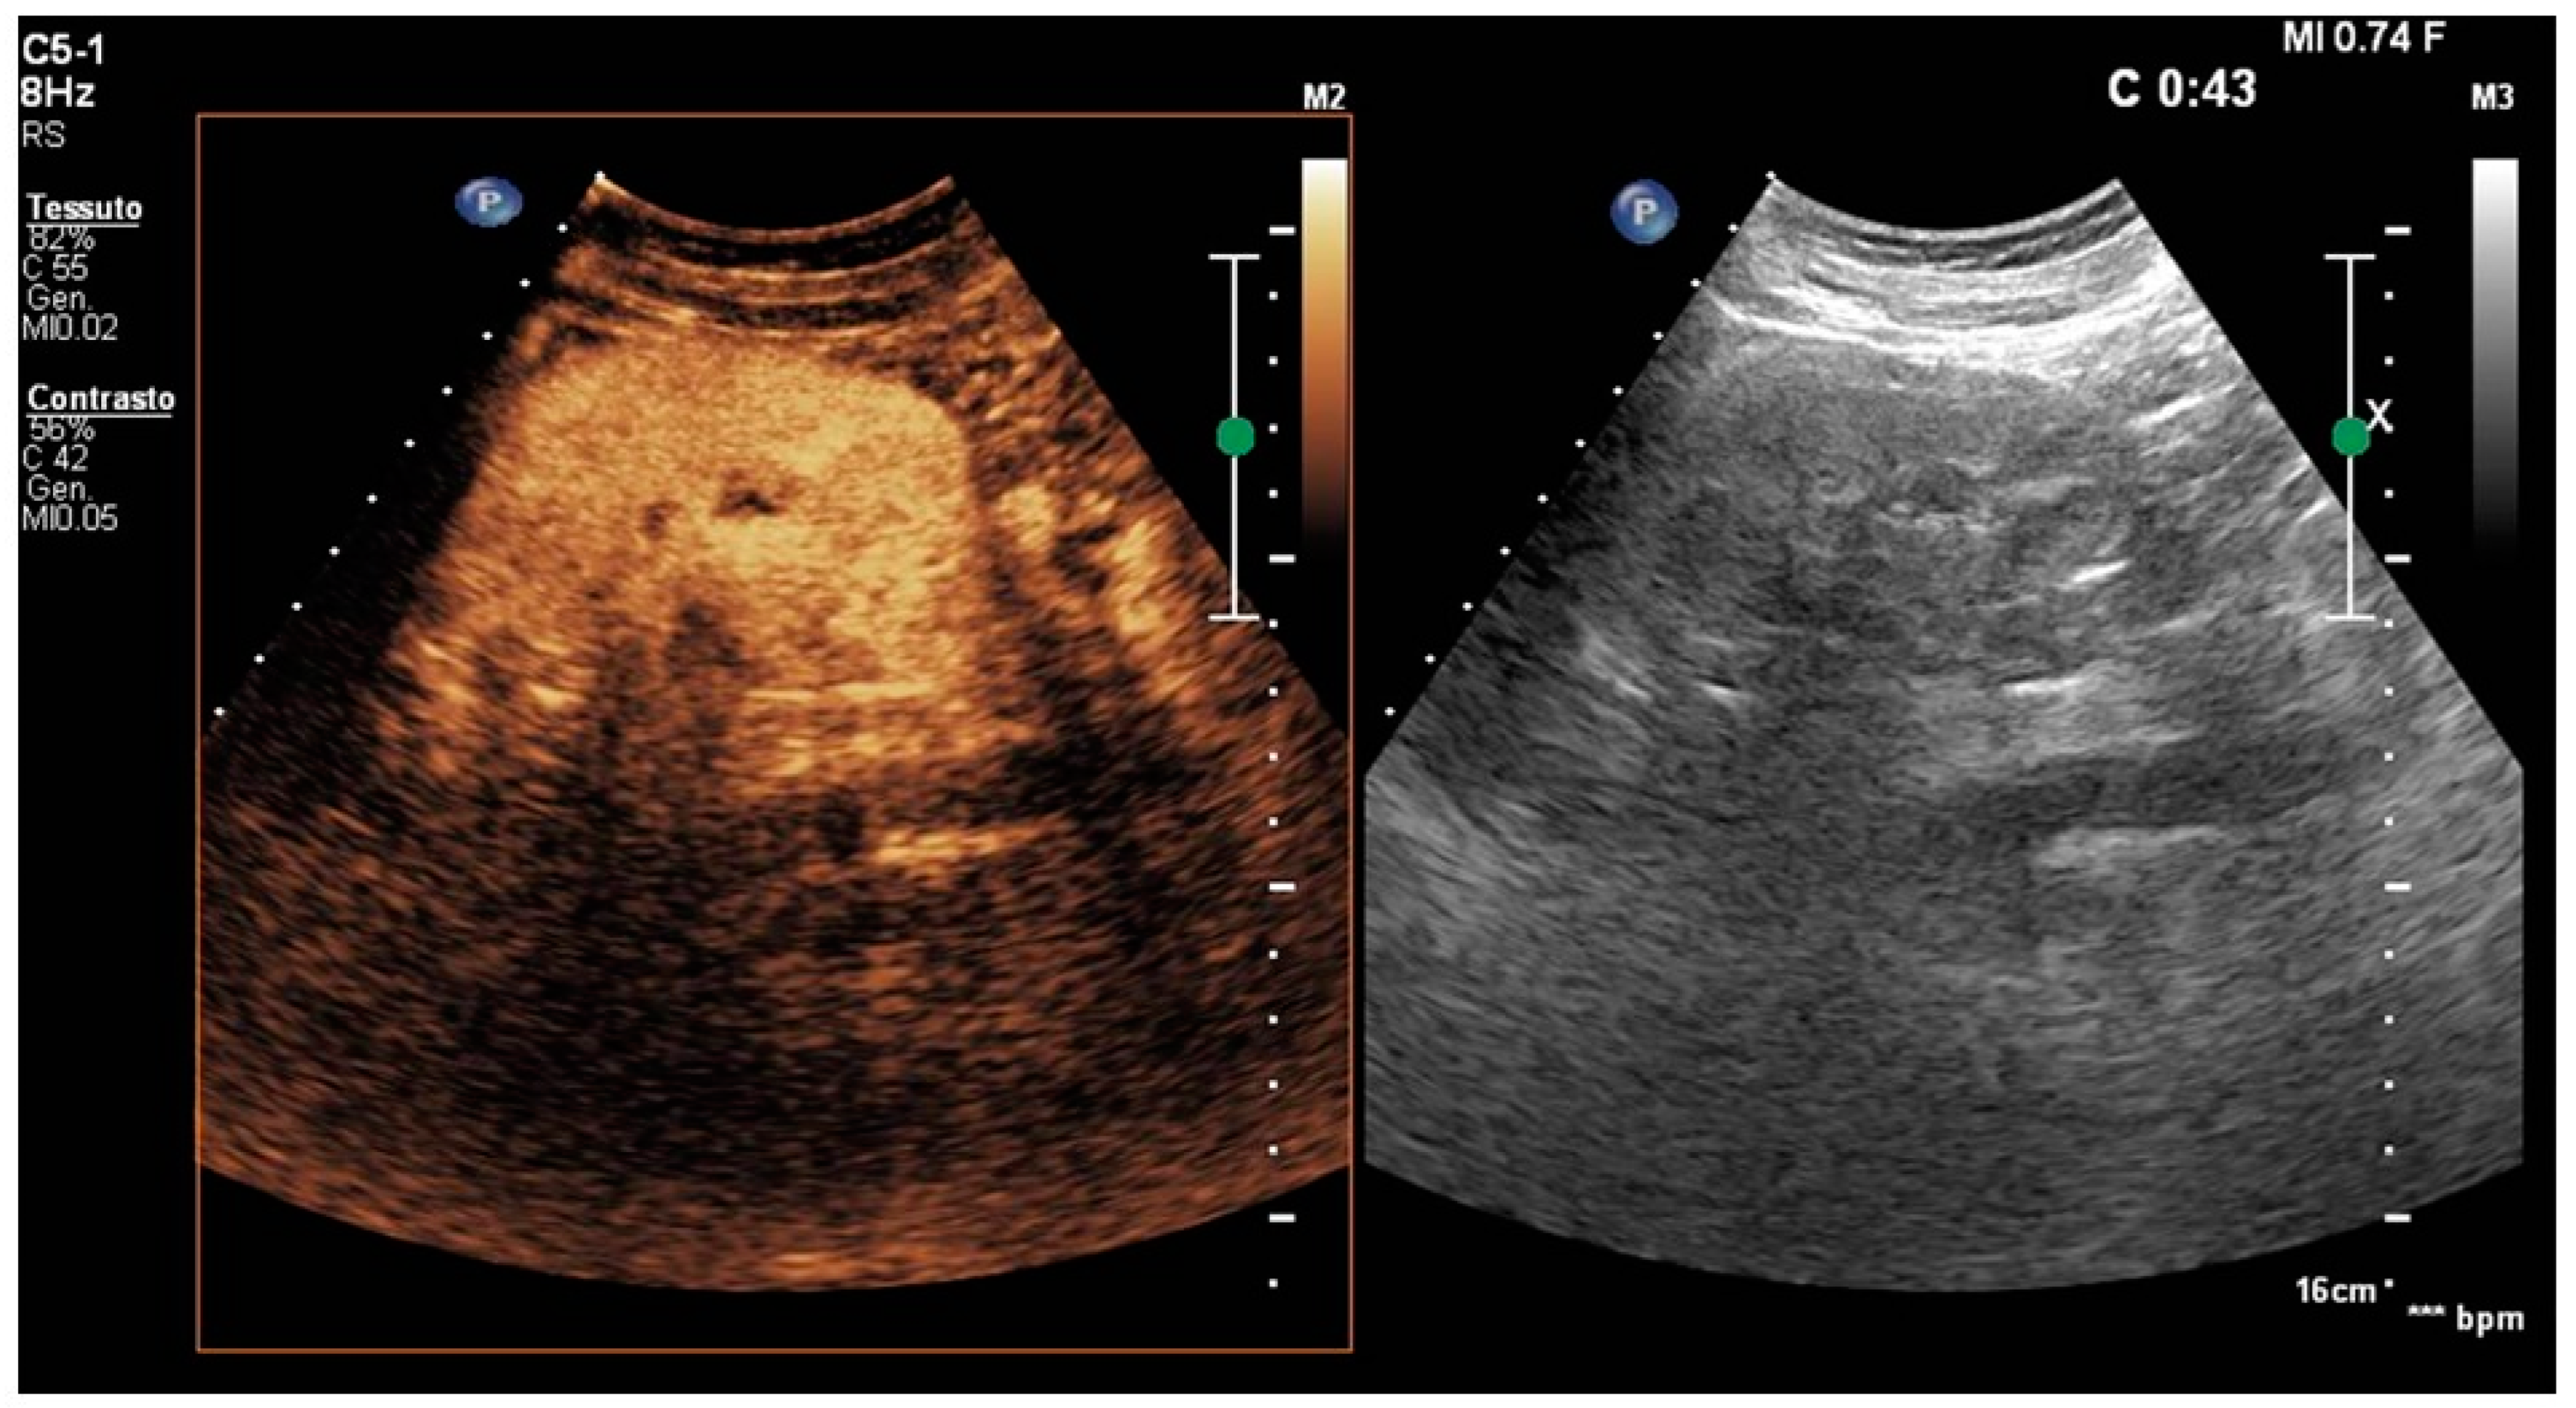

3. Results